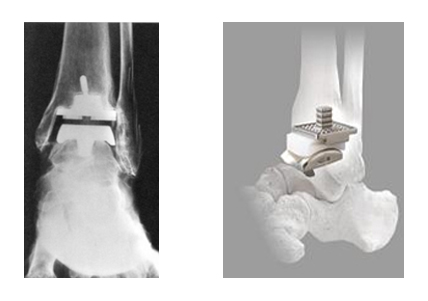

(上の図)下位脛骨骨切り術

脛骨の足首に近い部分で骨の向きを変えて、より軟骨が残っている部分に体重がかかる軸を移動させるものです。

これによって、軟骨が消失して狭くなった関節が開き、軟骨組織が再生することを促します。

第4期のように軟骨の摩耗が足関節全体に拡大しているときには、関節固定術もしくは人工足関節置換術が行われます。

足関節固定術では、足関節の傷んだ組織を切除し、脛骨と直下の距骨をスクリューで固定します。

足関節固定術を行うと、もはや関節が動かなくなるように感じられますが、そうではなく、足関節が固定されても、それ以外の足部の関節が動きますので、足首が完全に固定されるということにはなりません。

一方、人工足関節置換とは、軟骨を削って人工の関節を挿入するというものです。

人工足関節置換術により、痛みが軽快し、足首の可動域も確保できますが、耐用年数の問題があります。若い人には向きません。